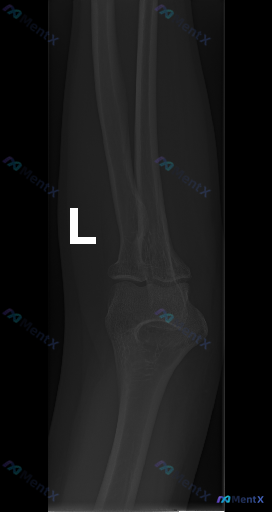

- 影像:左肘侧位X光片(只有侧位)

- 影像报告结论:各主要骨性结构皮质连续,关节对位良好,未见明显骨折脱位,脂肪垫无抬高,软组织无明显肿胀,骨骺已闭合。

- 矛盾点:有临床先验提示「存在异常」(但没给具体外伤史/体征)。

- 单凭这份侧位片,你会完全放心「没有问题」吗?最担心漏诊什么?

- 如果是你在急诊/门诊碰到这种「影像报没事但病人疼得厉害」的情况,下一步会怎么处理?